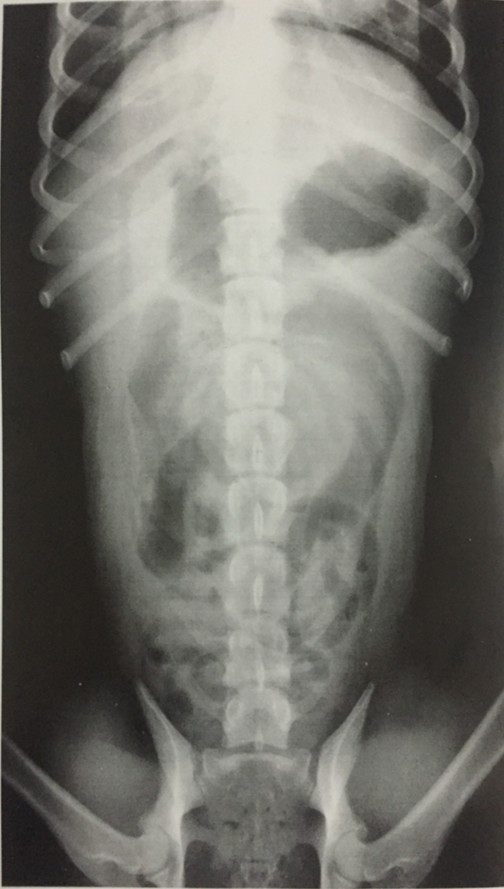

腹腔腹背位片示例 |

资源描述:动物仰卧保定,将前肢前拉,后肢自然摆放屈屈呈“蛙腿”样。X线束中心对准脐部,投照范围包含剑状软骨至耻骨的区域。